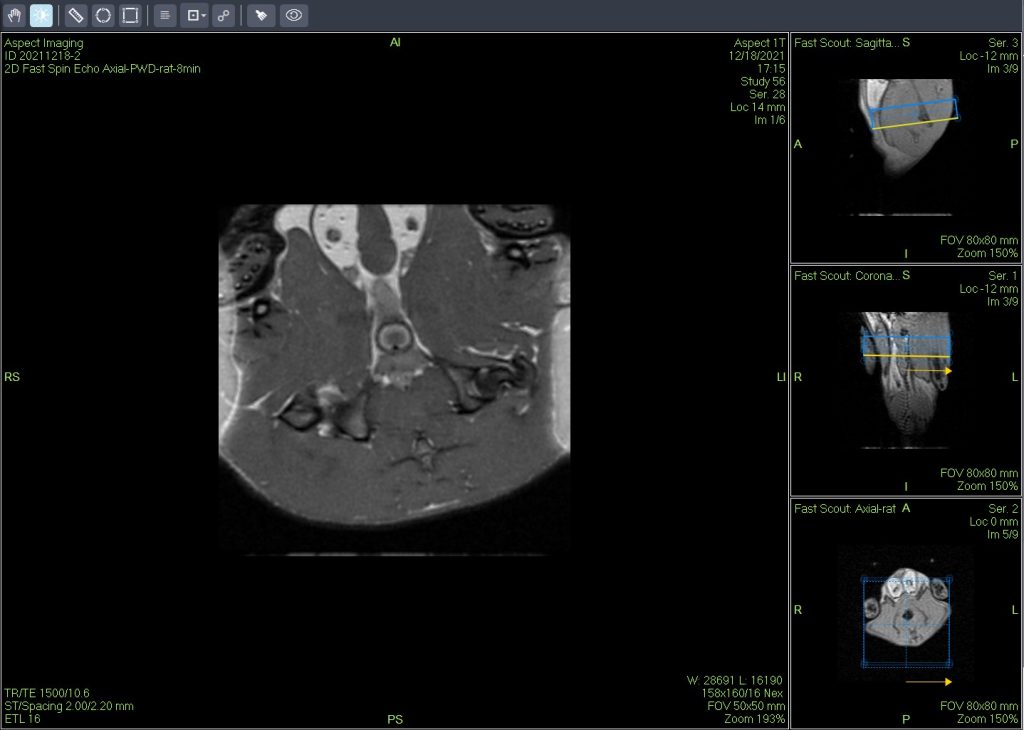

A new compact high-performance small-animal MRI platform (M3) combines an innovative magnet design with dedicated software to reduce the cost and complexity of traditional imaging systems. This new MRI platform enables pathologists without prior expertise in MRI or imaging to obtain high-quality in vivo MRI and ex vivo MRH images of laboratory animals. As a result, it greatly enhances conventional histopathological research in preclinical toxicology and animal disease-model development.

Unlike superconducting systems, the compact high-performance small-animal MRI platform is mobile and self-shielded. M3 can be installed in most laboratories or research facilities without the need for shielded rooms, cryogens, coolants, or specialised electrical or plumbing support. The platform also integrates dedicated hardware and software, pre-programmed protocols, and sample-handling systems—making high-throughput imaging of in vivo or ex vivo specimens straightforward for pathologists.

The advantages of the compact high-performance small-animal MRI platform include longitudinal monitoring of disease progression (in vivo MRI) and rapid acquisition of multiple ex vivo tissue slices (MRH). This provides detailed three-dimensional digital morphological data of entire target organs while keeping specimens intact for subsequent histopathological analysis. Compared with the limited two-dimensional slices from traditional histology, MRI offers a more comprehensive evaluation of toxicological effects and disease progression.

In vivo MRI detected focal liver injury in a mouse model (Fig. A). High-resolution ex vivo MRH identified several distinct focal fatty lesions in the liver (Fig. B and C). Routine histopathology confirmed these lesions as focal fatty changes (Fig. C).